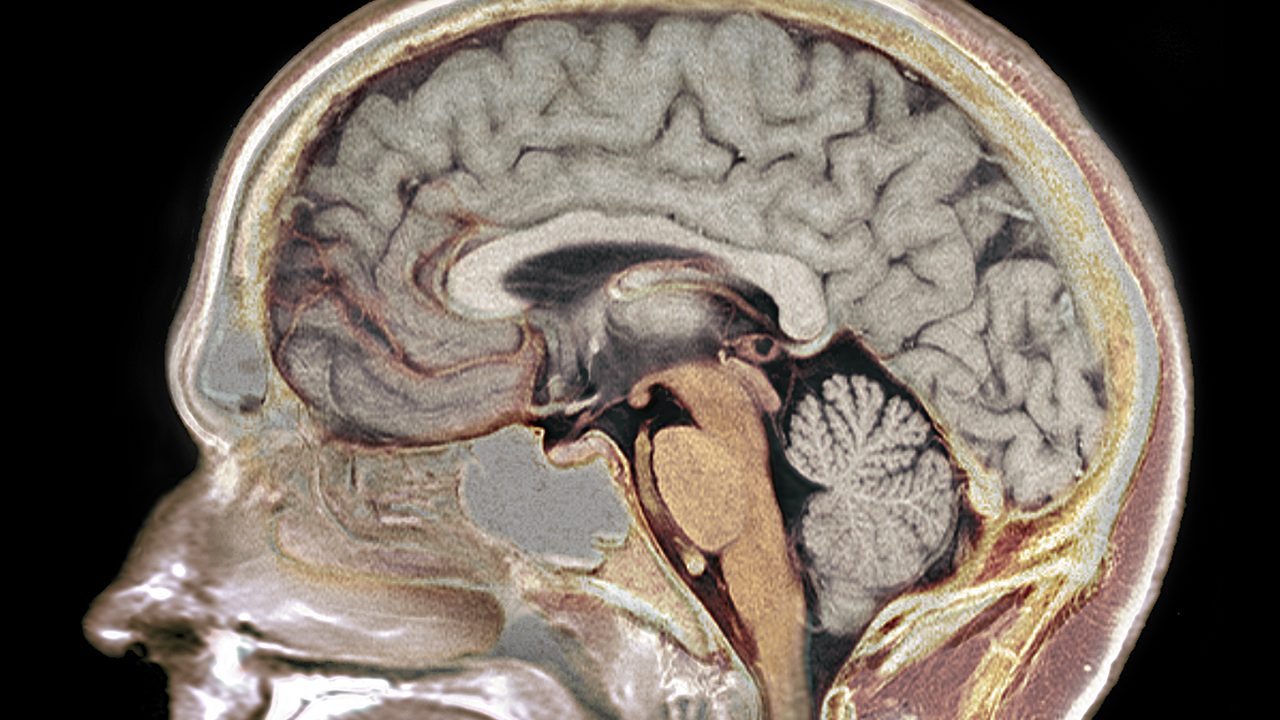

Например, шизофрения и биполярное расстройство. Симптоматика разная, но есть много генов, характерных для обоих этих заболеваний: около 70% генетических факторов риска шизофрении оказалось характерно и для биполярного расстройства. Или СДВГ (синдром дефицита внимания и гиперактивности) и аутизм, которые в психиатрических справочниках классифицируются даже не как разные заболевания, а как целый спектр из множества заболеваний, но с точки зрения генетики все они имеют общую базу, во всяком случае — общие генетические корреляты. Важно, что некоторые из этих генов активны уже в формирующемся мозге эмбриона, задавая базовые особенности его нейроархитектуры.

- шизофрения и биполярное расстройство — оказалось, важную роль в возникновении этих расстройств играют нарушения в работе возбуждающих нейронов и формируемых ими синапсах в коре и гиппокампе;